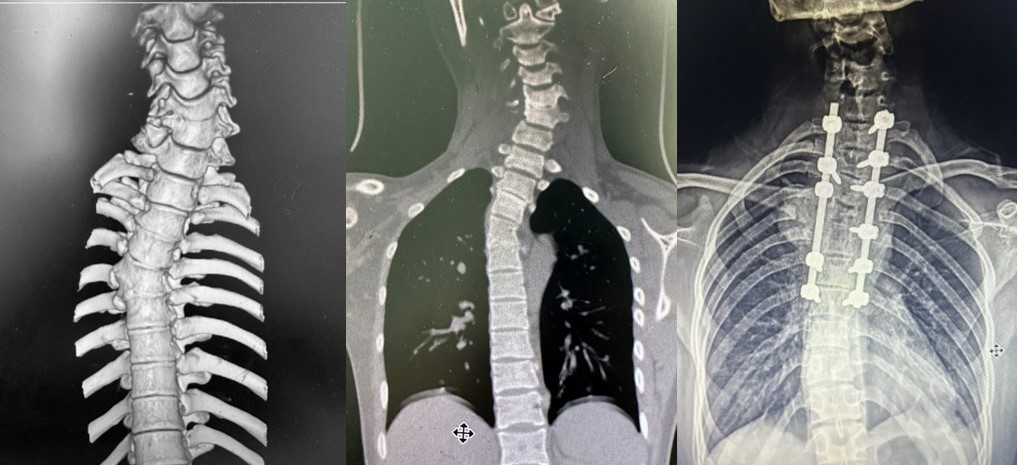

病例2是一名18岁的大一新生,由于颈胸部半椎体畸形导致的头颈部偏斜、肩部不平衡、以及继发面部发育不对称等已严重影响日常生活及身心。患者及家长慕名而来,希望通过手术治疗改善病情。经过团队的详细评估和精心准备,由蔡璇副主任及王瑞主治医师为患者实施了脊柱截骨矫形植骨融合内固定术,为其未来的成长之路奠定了坚实基础(图2)。

病例2:颈胸段椎体分节不全伴发育不良,行脊柱截骨矫形术